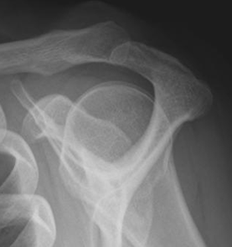

Como en todas las articulaciones, se debe iniciar la valoración con radiografía (Rx) simple. Con esta modalidad se pueden identificar lesiones focales, calcificaciones anormales, valorar lesiones traumáticas, etc.

Estructuras óseas a tener en cuenta: Cabeza del húmero, glenoides, apófisis coracoides, acromión y clavícula distal. (Fig 7).